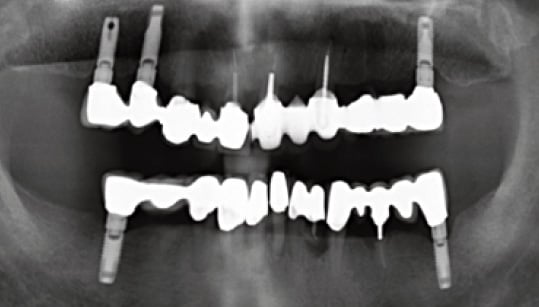

A patient in his early 80s presented with the chief complaint of recurrent pain, discomfort and swelling from his lower dentition. An examination revealed moderate to advanced bone loss of his remaining mandibular teeth.

Peri-apical radiolucencies associated with chronic apical periodontitis were also diagnosed on the lower anterior segment. His lower dentition at the time of presentation was restored with fixed crown and bridge prosthesis with implant fixtures on the 37 and 47 site, placed 20 years prior. The implant fixtures were abutments for fixed bridges that were linked to natural teeth abutments (Fig. 1).

Failed lower dentition and very old steriosis implants

Fig. 1. Failed lower dentition and very old steriosis implants